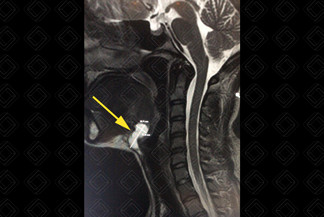

Texto alternativo para a imagem Figura 3. Créditos: Dra. Elazir Mota - Rio de Janeiro/RJ

Descrição da figura 3: Ressonância magnética do pescoço. Sequência ponderada em T2, sagital. Imagem cística, hiperintensa em T2, localizada na linha média, sugestiva pela localização e características de imagem de cisto tireoglosso (seta amarela).

• Ressonância magnética do pescoço: Alto sinal nas imagens ponderadas em T2 e baixo sinal em T1 (nos cistos não complicados). Quando complicados, com sangramento ou infecção, podem exibir sinal aumentado em T1. Após a administração do contraste venoso, não há realce. Caso infectado, a parede do cisto pode apresentar realce pós-contraste (figura 3).